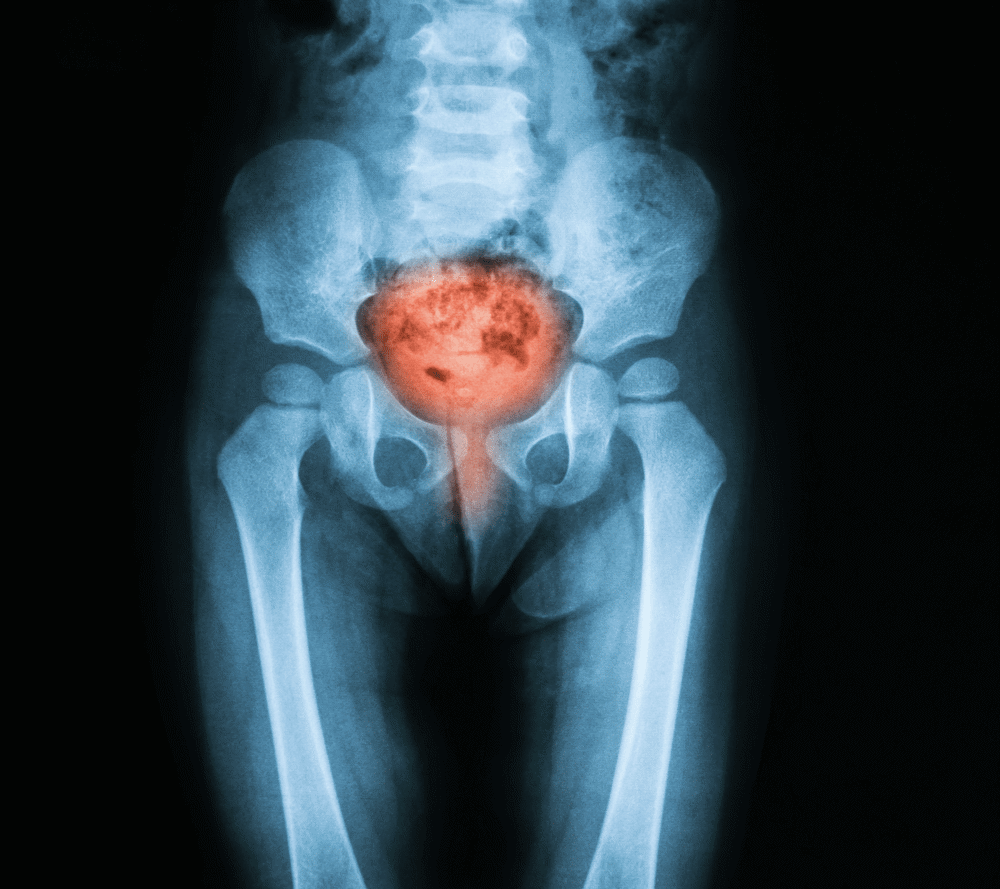

Image Credit: Suttha Burawonk / Shutterstock.com